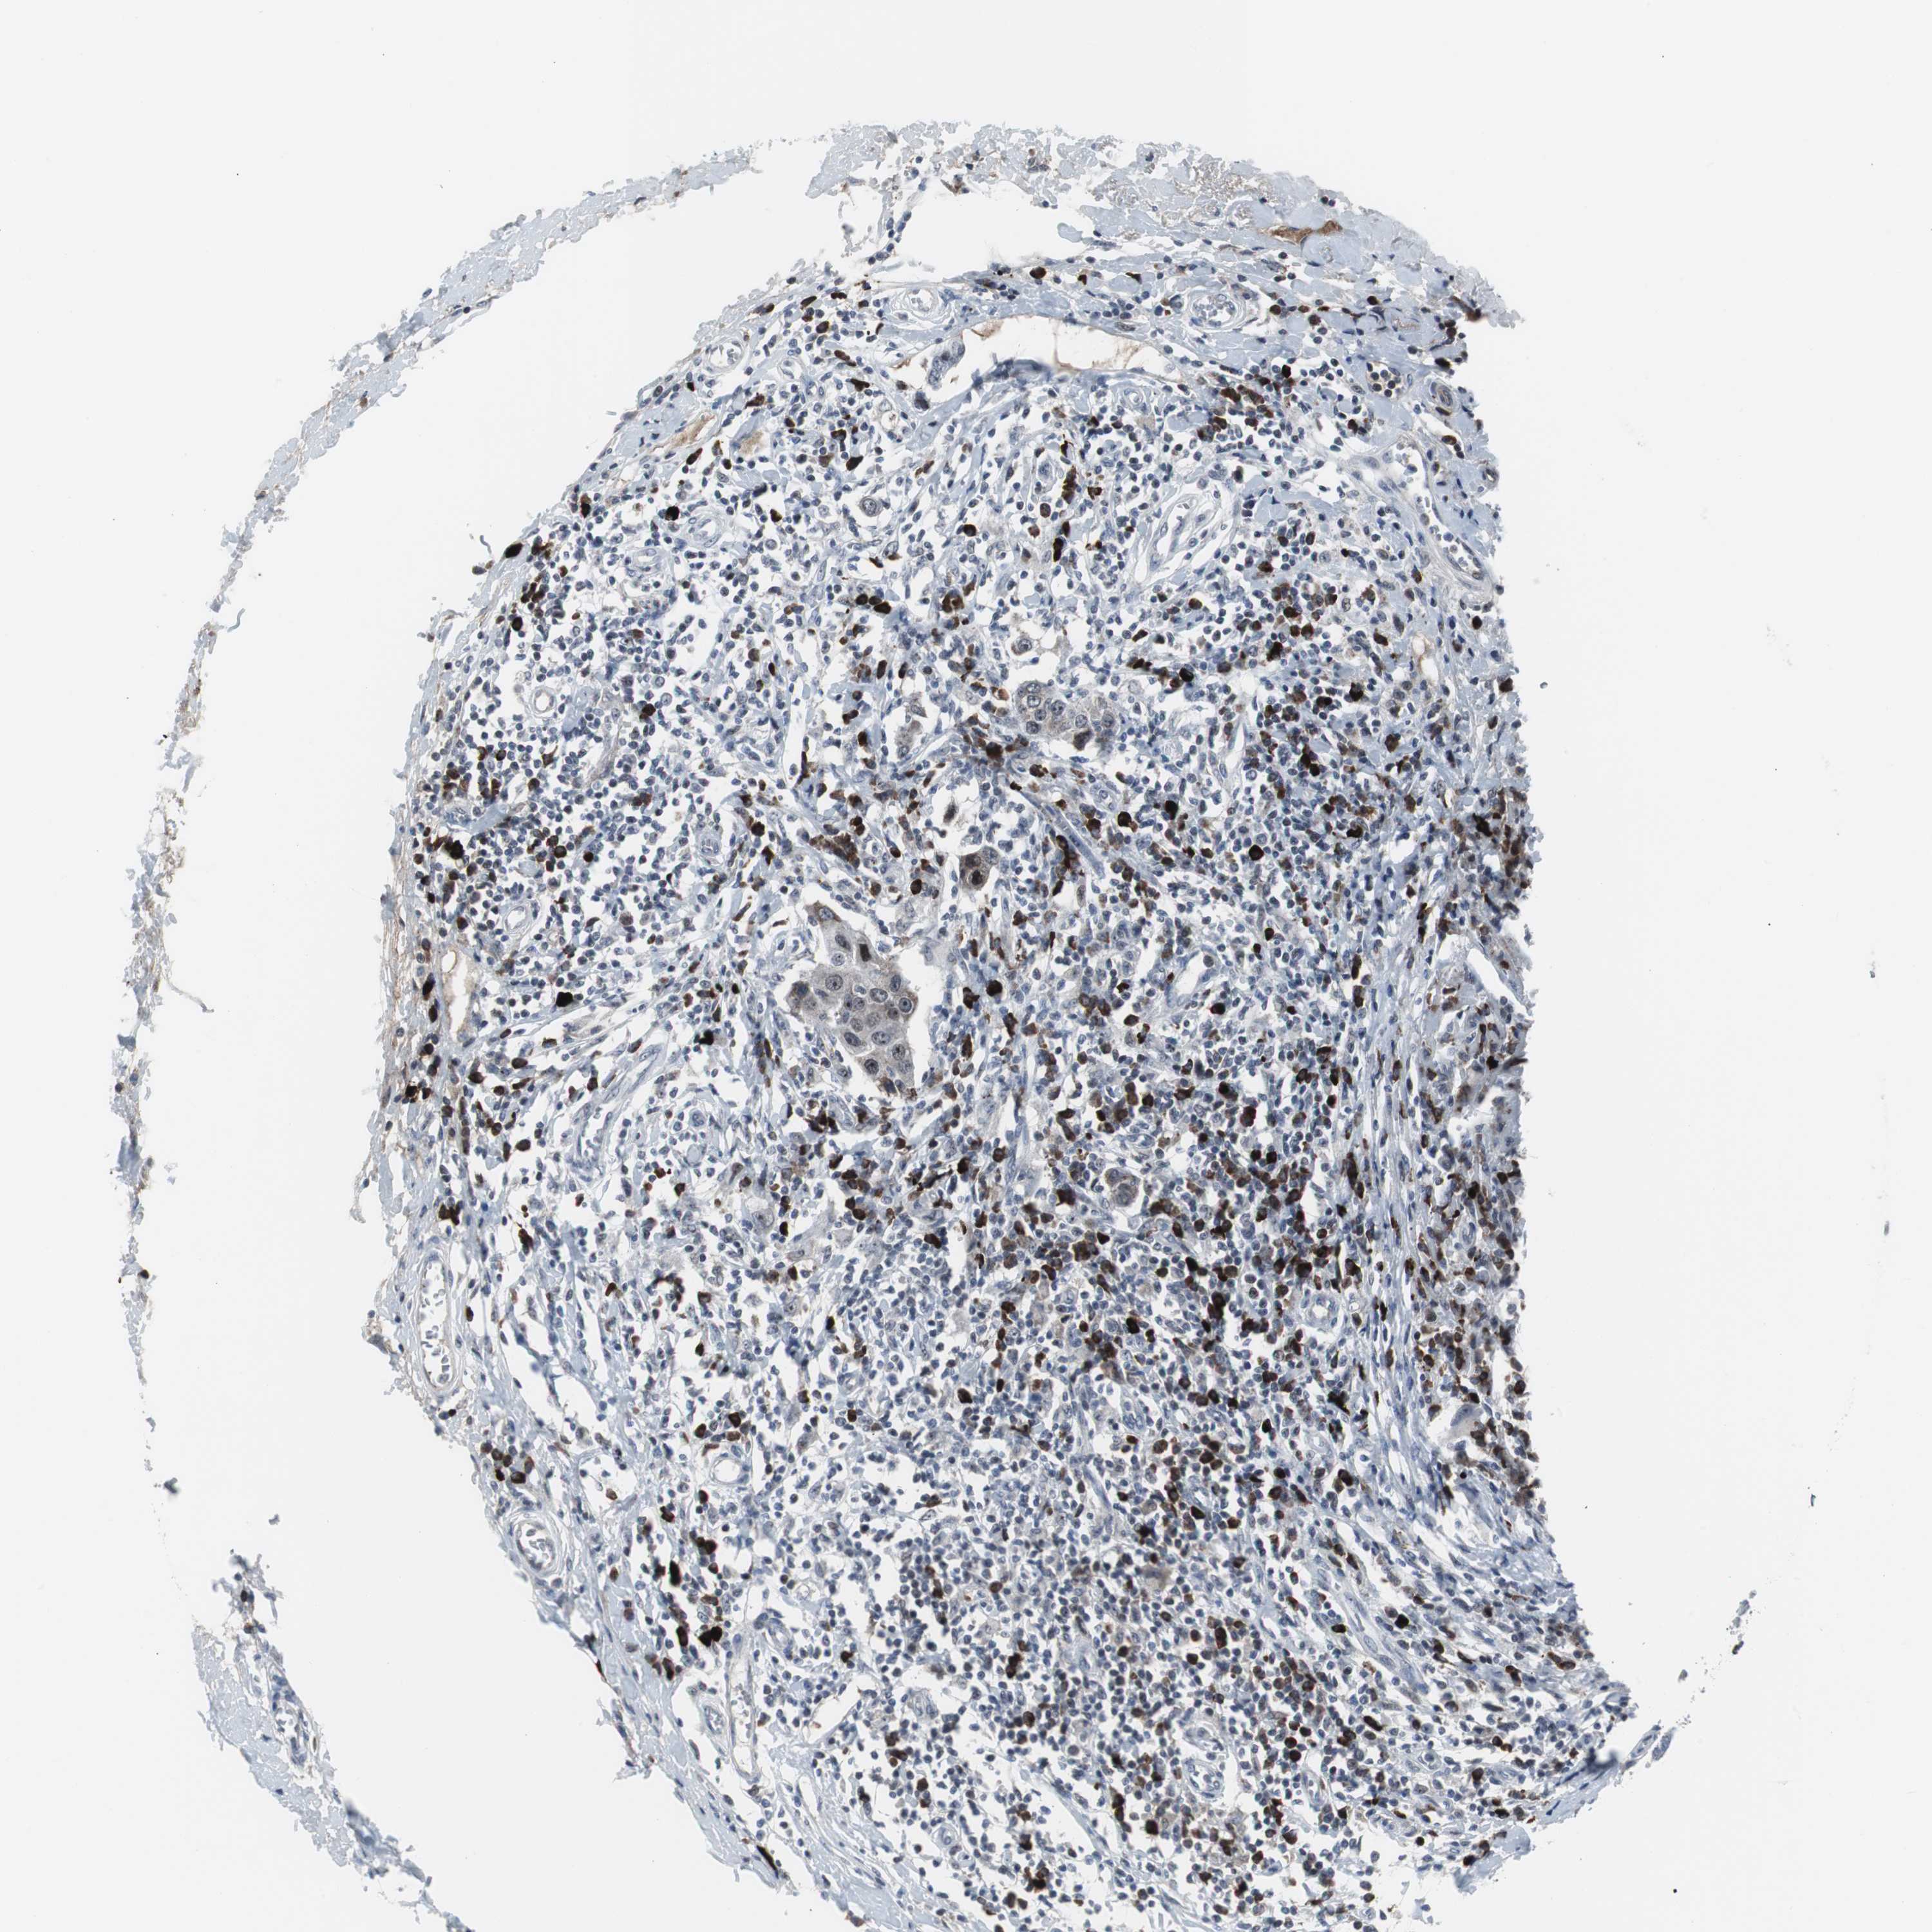

BRCA TCGA BRCA VALIDATION PROTEIN EXPRESSION